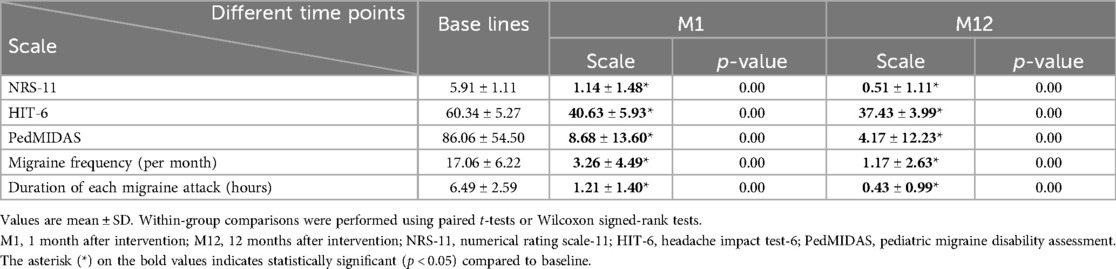

Patients underwent intervention under general anaesthesia and transesophageal ultrasound monitoring using an 18/18 mm PFO occluder (Huayi Shengjie Co., Ltd., Beijing, China). After general anaesthesia, patients were positioned supine, disinfected, and covered with a towel. The right femoral vein (RFV) was punctured, a 6 Fr vascular sheath was inserted, and a 5 Fr multifunctional catheter was inserted through the RFV to the fossa ovalis. A loach guidewire was inserted through the foramen ovale into the left upper pulmonary vein, and a multifunctional catheter was inserted along the loach guidewire into the left upper pulmonary vein. The loach guidewire was then pulled out, a 260 cm 0.035-in exchange guidewire was sent through a 5 Fr multifunctional catheter and fixed in the left upper pulmonary vein, and the 6 Fr delivery sheath was transported along the guide wire to the left upper pulmonary vein opening. The inner sheath and guidewire were then pulled out and the occluder was sent along the long sheath to the left atrium. The left atrial umbrella was released, the right atrial umbrella was released into the right atrium, and the atrial interval was fastened. Intraoperative oesophageal ultrasound was used to observe whether the occluder had any effect on the surrounding structures. If there was no effect, the occluder was released and local pressure was applied to stop bleeding. An 18/18 mm occluder was used in all operations. Dual antiplatelet therapy with aspirin (3–5 mg/kg/d, max 100 mg) and clopidogrel (1 mg/kg/d, max 75 mg) was administered post-intervention for three months, followed by aspirin monotherapy for an additional three months. All antiplatelet medications were discontinued after six months. The PFO occlusion procedure in illustrated in Figure 3. Ultrasound changes before and after intervention are reported in Figure 4.

Figure 3. Patent foramen ovale occlusion. (A) The guidewire enters the left upper pulmonary vein under digital subtraction angiography (DSA) guidance; (B) a multifunctional catheter is advanced into the left upper pulmonary vein under DSA guidance; (C) the stiff guidewire is introduced into the left upper pulmonary vein under DSA; (D) the delivery sheath is sent to the left atrium along the stiff guidewire; (E) the delivery sheath is transferred to the left chamber; (F) the occluder is deployed in the oval hole; (G) the occluder is released in the left front oblique position and the occluder is in the tangential position; (H) The position of the occluder is satisfactory.